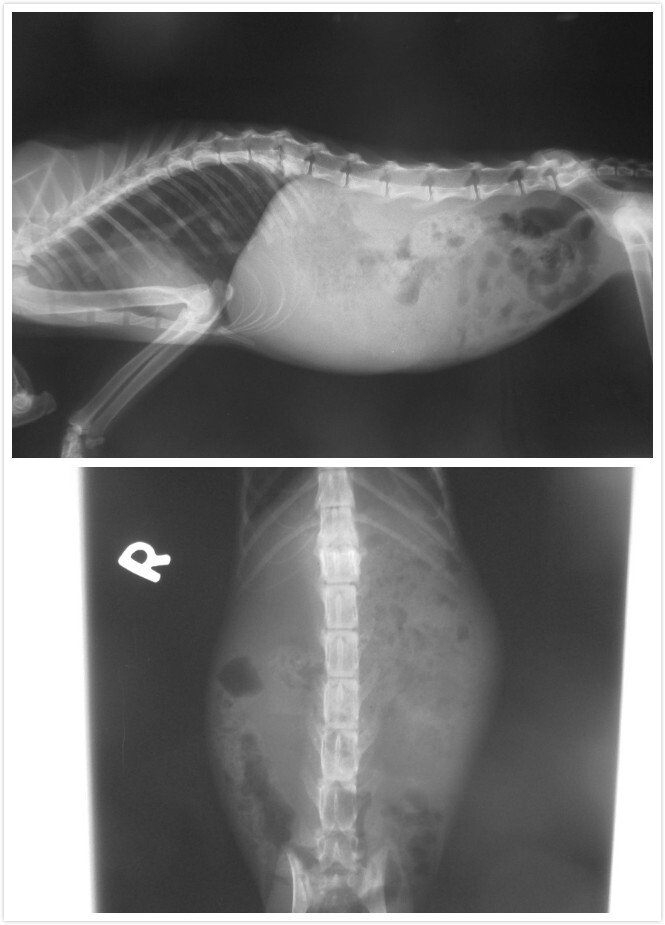

醫生說~~小美疑似被車撞擊又被遺棄在公園那裡~~小美有T13及L1椎體骨折及脊椎神經受損的現象,雖有痛覺反應但本體反射消失,會自主排尿但目前並無排便,後腳有外傷,血檢有白血球過高,貧血及脫水的現象,初步先止痛,藥物及輸液治療,建議轉診至有開脊椎手術的醫院評估治療~~

小美住院的這幾天~~也還特地跑道協會的配合醫院去檢查~~醫生看了一下X光片也說~雖然前後有痛的反應~但怕在當時撞擊時中間神經不知道有沒有斷掉~雖然骨頭看來可以靠手術固定~但就是怕神經的部分~如果神經部分斷了~就算開刀也沒用><還是一樣癱瘓~~